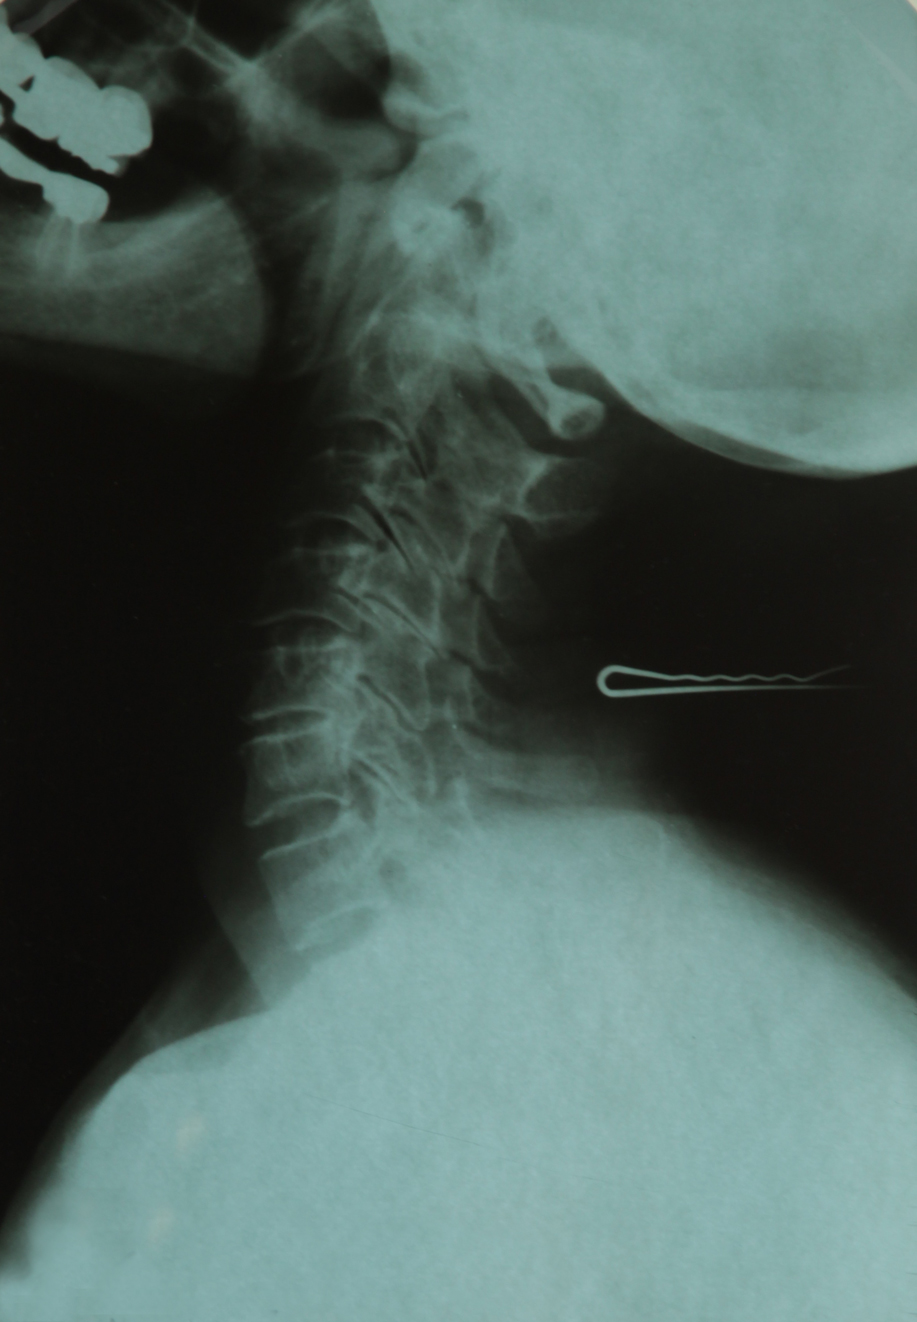

X-RAY. A Family Album (série de 5 radiographies)

Dans son essai Strahlen der Gewalt (Les rayons de la violence), Shahram Khosravi souligne l'importance sociale du regard radiographique : « Le regard médical de l'appareil à rayonsX fonctionne comme un instrument biopolitique qui régule et discipline les corps dans le cadre de la détermination de l'âge des demandeurs d'asile, des demandes de visa des migrants, de la commercialisation des femmes et de la criminalisation des mineurs.SilatechnologiedesrayonsXpermetd'unepartdesauverdesvies, elleestd'autrepartunoutildecontrôleetd'oppression. »